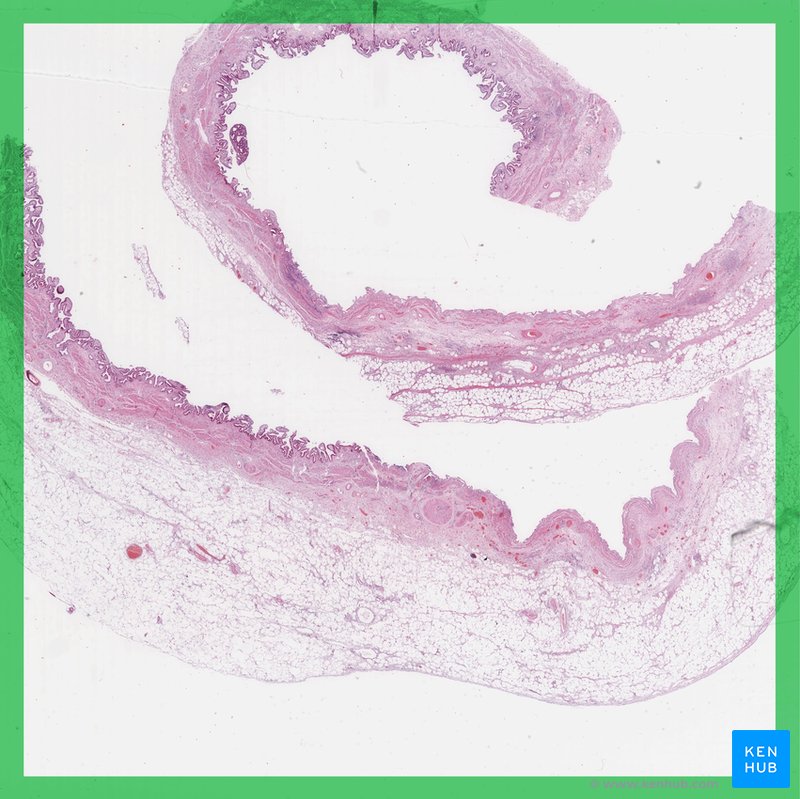

Accessory Organs Of Digestive System . Chemical digestion in the small intestine relies on the activities of three accessory digestive organs: Chemical digestion in the small intestine relies on the activities of three accessory digestive organs: Learn about the liver, gallbladder, and pancreas, the major accessory organs of digestion that secrete substances for chemical digestion in. Find out how bile, enzymes, and buffers help break down lipids, proteins, and carbohydrates in. Your digestive system is a network of organs that help you digest and absorb nutrition from your food. Accessory organs of digestion are organs that secrete substances needed for the chemical digestion of food but through which food does. The liver, pancreas, and gallbladder (figure 21.7.1). These accessory organs of digestion play key roles in the digestive process. The digestive role of the liver is to. The salivary glands, liver and gall bladder, and the pancreas aid the processes of ingestion, digestion, and absorption. Learn about the digestive roles, histology, and functions of the liver, pancreas, and gallbladder.